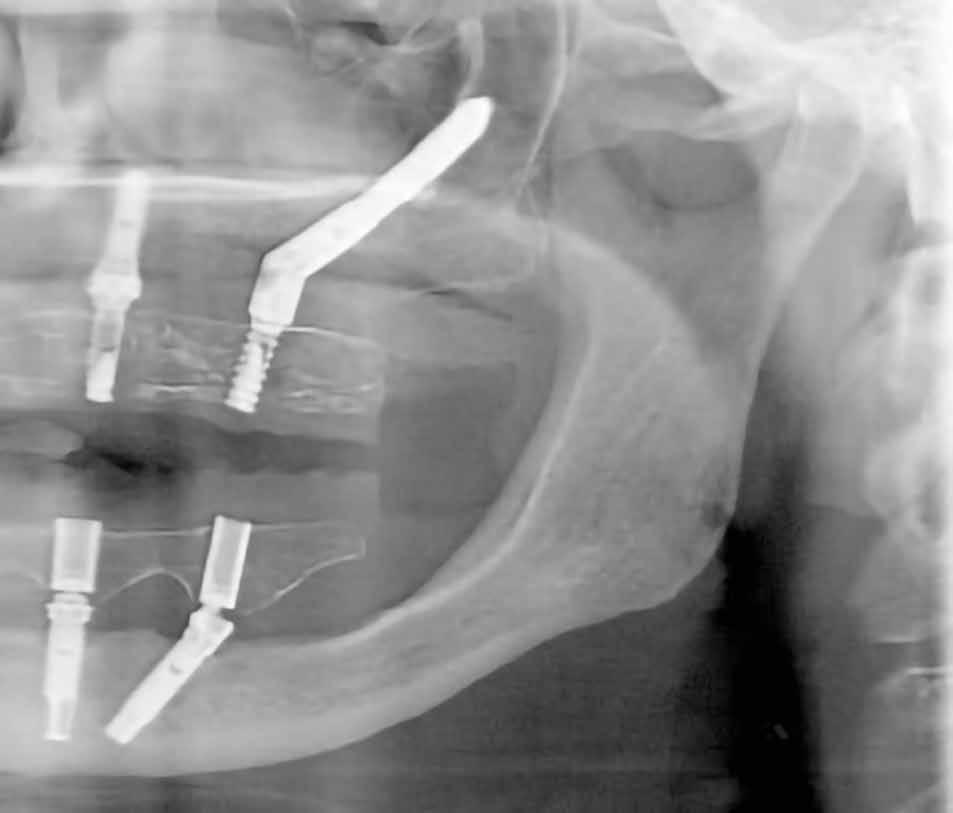

A 64 éves kaukázusi nőpáciens 2004 óta áll gondozásunk alatt, az alsó fogíven sikeres All-on-4 kezelésen van túl (1. ábra). Felső állcsontja több mint harminc éve fogatlan, de erősen motivált a sebészi rehabilitációra. A páciens elsődleges célja egy fix fogpótlás volt, amely helyreállítja a rágófunkciót és az esztétikus megjelenést (2. ábra).

Mindkét kvadránsba behelyeztünk (>50 Ncm behajtási nyomatékkal) egy-egy 5 mm átmérőjű és 42,5 mm hosszúságú implantátumot (Nobel Zygoma 0°, Nobel Biocare), a második nagyőrlők helyére (4. ábra). Az implantátumok tengelyállásának kompenzálására 45°/6 mm magasságú tengelykorrekciós multi-unit fejeket használtunk (Multi-Unit Abutment, Nobel Biocare), amelyeket 30 Ncm nyomatékkal húztunk meg [17].

A frontrégióban (1.3 és 2.1) egy-egy 3,3 mm átmérőjű és 11,5 mm hosszúságú implantátumot (Nobel Speedy Groovy, Nobel Biocare) helyeztünk be, szintén >50 Ncm behajtási nyomatékkal, amelyekre 3 mm (1.3 helye) és 2 mm (2.1 helye) magas multi-unit fejek (Multi-Unit Abutment, Nobel Biocare) kerültek, 25 Ncm nyomatékkal meghúzva (5. ábra). A lebenyeket visszafektettük, majd a műtéti területet varrattal zártuk (4/0 selyem; B. Braun Medical; 6. ábra).

21. ábra: A hangár technika okkluzális nézetből. – 22. ábra: A posztoperatív panorámaröntgen, amelyen látszik a jobb felső kvadráns augmentált területe. A hangár technika lehetővé tette az augmentáció és az implantáció egyidejű elvégzését. 23. ábra: A feltárás és a gyógyulási fej behelyezése. – 24. ábra: A feltárást követően készült panorámafelvétel, amelyen a gyógyulási fej látható.